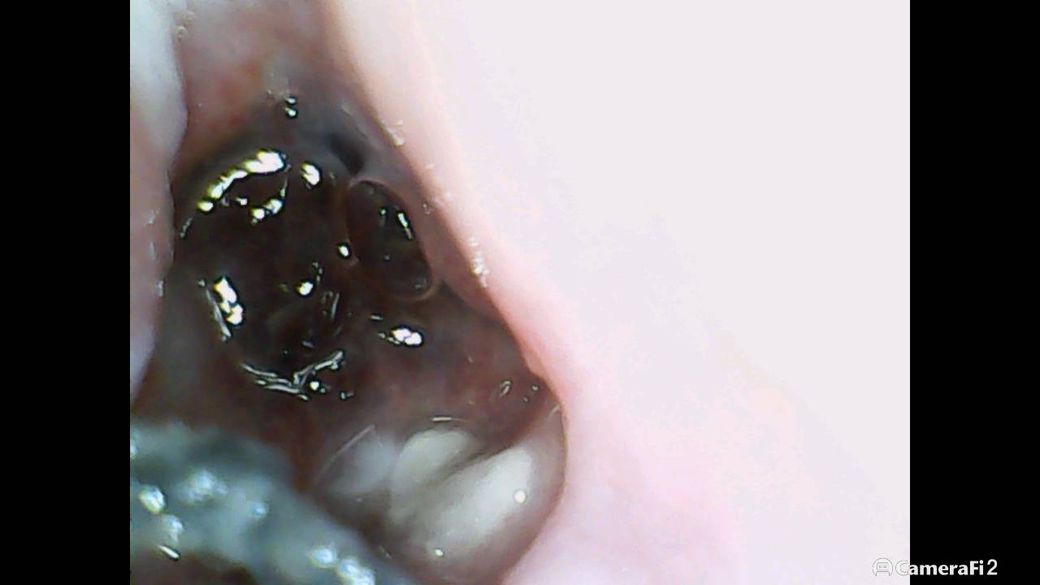

사진은 아래쪽 사랑니 발치 부위입니다.

(앞쪽 검정색은 봉합실입니다)

발치 부위에 보이는 하얀색이 잇몸뼈인가요??

아니면 안쪽잇몸이 아무는 과정인것일까요?

• 1번 째 사진